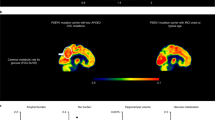

The male patient was enrolled in the Colombia–Boston biomarker research study (COLBOS) and underwent neuroimaging examinations at the Massachusetts General Hospital (MGH) when he was 73 years old (see Supplementary Table 2 for the demographic information). Amyloid positron emission tomography (PET), measured using cortical-to-cerebellar Pittsburgh compound B (PiB), revealed that the individual’s levels of cortical amyloid beta (Aβ) plaque burden were higher (distribution volume ratio (DVR) = 1.77) compared to that of younger impaired carriers from this kindred with a typical age at onset (mean DVR = 1.51 ± 0.13; Fig. 1a,b). Tau tangle burden in the inferior temporal lobe, measured by flortaucipir (FTP), was similar to that seen in younger PSEN1-E280A impaired carriers with typical age at onset (standardized uptake value ratio (SUVR) = 1.78). However, he had relatively limited Tau pathology in the entorhinal cortex (ERC) (SUVR = 1.34; Fig. 1a,c) and in other neocortical regions, such as the posterior cingulate cortex (PCC) and precuneus (SUVR PCC = 1.51; SUVR precuneus = 1.49; Fig. 1a), which usually show greater levels of Tau pathology in PSEN1-E280A carriers who develop MCI and dementia at a typical age3 (Fig. 1, Supplementary Fig. 2 and Extended Data Figs. 1 and 2). Sparing of the ERC from Tau pathology is a salient feature in the case with RELN-COLBOS that could be critical for the protection phenotype.

a, Representative PiB PET amyloid and FTP Tau PET imaging of the male case with RELN-COLBOS (left) compared to a PSEN1-E280A mutation carrier with MCI at a typical age (right). For both measurements, specific binding of the tracer is represented using a color-coded scale with blue being the lowest (DVR or SUVR = 0.8) and red being the highest (DVR or SUVR = 2.00) degree of binding. Right, representative FDG PET precuneus cerebral metabolic rate for glucose (CMRgI) of the male case with RELN-COLBOS (left) compared to a PSEN1-E280A carrier with MCI at a typical age (right). Binding affinity of the dye is represented using a color-coded scale with blue being the lowest (SUVR = 0.5) and red being the highest (SUVR = 2.1) degree of binding. PHF, paired helical filament. b, Dot plot analysis of the imaging measurements shown in a for amyloid and Tau burden, glucose metabolism and hippocampal volume. Brain imaging measurements of the male case with RELN-COLBOS (red dot) compared to the previously published APOECh homozygote female (blue dot), unimpaired PSEN1-E280A carriers (gray dots, n = 18 for the glucose metabolism panel, n = 13 for all other panels) and younger carriers of the MCI PSEN1-E280A mutation (black dots, n = 7 for the Tau burden plot, n = 8 for the amyloid burden and hippocampal volume plots, n = 11 for glucose metabolism)2. Some previously published data points are included in the figures because they are the only available data for comparison2. Data are expressed as individual values with the mean ± s.e.m. c, Anatomical details of Tau burden in the temporal cortex. Flat map representations of the right hemisphere temporal lobe cortex for regions of interest (ROIs) (top left, ERC), with Tau PET (FTP) overlay for four cases. The asymptomatic PSEN1-E280A carrier was 38 years old; the PSEN1-E280A carrier with typical MCI was 44 years old. The male carrier of RELN-COLBOS was notable for having relatively lower Tau burden in the medial temporal regions (ERC and PPC), compared to typical PSEN1-E280A mutation carriers.

Measurements of metabolic rate for glucose in the precuneus and whole brain region using 18F-fluorodeoxyglucose (FDG) PET showed a slightly higher level of glucose metabolism compared to the mean levels of typical MCI carriers from the kindred, who were much younger (Fig.1a,b). He had brain atrophy, measured by magnetic resonance imaging (MRI)-based hippocampal and whole brain volume typical of MCI carriers. These imaging findings suggest that in this patient and in the APOECh homozygote case2, protection against ADAD dementia occurred even in the face of high amyloid burden (Fig. 1a,b). Additional imaging and biomarker analyses are reported in the supplementary results of the Supplementary Information.